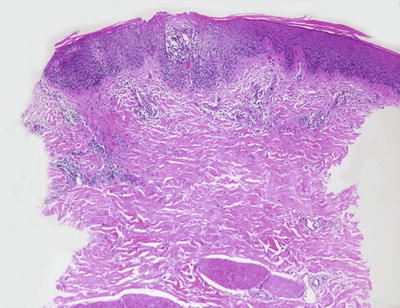

Histologic changes in acute atopic dermatitis are quite subtle. Scant wispy parakeratosis overlies an epidermis that demonstrates slight spongiosis and small collections of Langerhans cells [3] (Fig. 1.2). Scattered eosinophils may be present in the superficial dermis, admixed with increased numbers of lymphocytes [4] (Fig. 1.3). Degranulated mast cells may be present but are rarely observed on routine histologic sections. A folliculocentric pattern with spongiosis concentrated within follicular infundibula has been described, and is more common in darker skinned individuals [5].

Fig. 1.3

A spongiotic dermatitis with scant exocytosis of lymphocytes is seen in atopic dermatitis